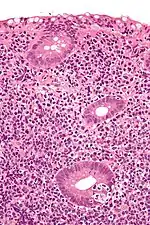

Micrograph showing a lymphoepithelial lesion (lower right of image) in a primary gastrointestinal tract lymphoma. H&E stain.

In pathology, lymphoepithelial lesion refers to a discrete abnormality that consists of lymphoid cells and epithelium, which may or may not be benign.

It may refer to a benign lymphoepithelial lesion of the parotid gland or benign lymphoepithelial lesion of the lacrimal gland, or may refer to the infiltration of malignant lymphoid cells into epithelium, in the context of primary gastrointestinal lymphoma.[1]

In the context of GI tract lymphoma, it is most often associated with MALT lymphomas.[1]